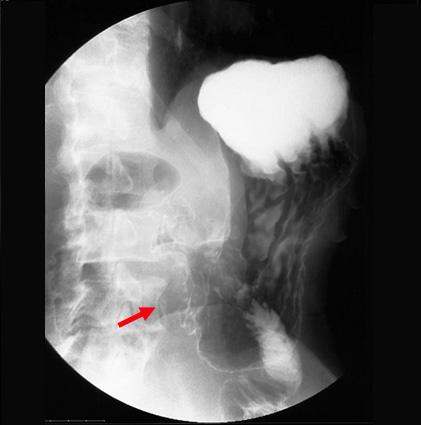

clasificación del pacienteTumor Epitelial Maligno/Adenocarcinoma

parte(separada por órganos)estómago(región)/antro

método de exámenRayos X

clasificación ectoscópica de tumoresTipo 3(Tipo ulcerado de bordes infiltrados)/

diámetro mayor del tumor40 -

grado de penetracións(a)